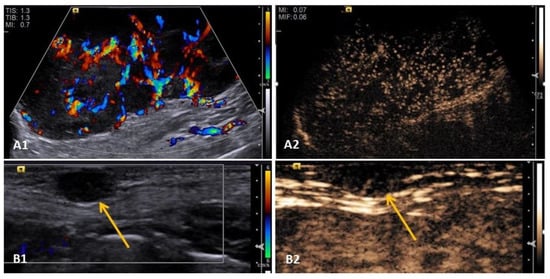

3.2. Doppler Ultrasonography

3.3. Elastography

3.4. Contrast-Enhanced Ultrasound (CEUS)

- Feliciano, M.A.R.; Ramirez, R.A.U.; Maronezi, M.C.; Maciel, G.S.; Avante, M.L.; Senhorello, I.L.S.; Mucédola, T.; Gasser, B.; Carvalho, C.F.; Vicente, W.R.R. Accuracy of four ultrasonography techniques in predicting histopathological classification of canine mammary carcinomas. Vet. Radiol. Ultrasound. 2018, 59, 444–452. [Google Scholar] [CrossRef] [PubMed]

- Feliciano, M.A.R.; Vicente, W.R.R.; Silva, M.A.M. Conventional and Doppler ultrasound for the differentiation of benign and malignant canine mammary tumours. J. Small Anim. Pract. 2012, 53, 332–337. [Google Scholar] [CrossRef]

- Navarro, D.M.; Silva, D.M.F.; Costa, F.S.; Wischral, A. Dopplerfluxometric and angiogenic analysis of canine mammary tumors. Arq. Bras. Med. Vet. 2018, 70, 1099–1108. [Google Scholar] [CrossRef]

- Abma, E.; Stock, E.; De Spiegelaere, W.; Van Brantegem, L.; Vanderperren, K.; Ni, Y.; Vynck, M.; Daminet, S.; De Clercq, K. Power Doppler ultrasound and contrast-enhanced ultrasound demonstrate non-invasive tumour vascular response to anti-vascular therapy in canine cancer patients. Sci. Rep. 2019, 9, 9262. [Google Scholar] [CrossRef] [PubMed]